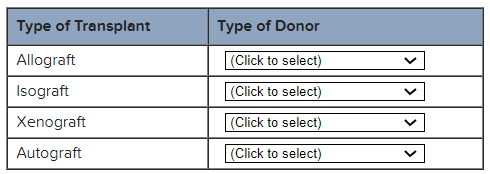

For each classification of transplant, indicate the correct type of donor.